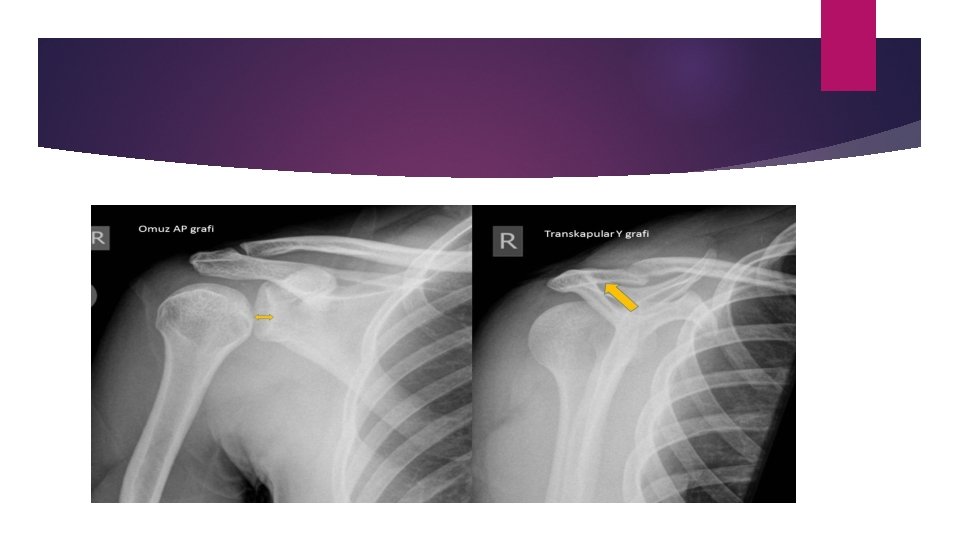

Radyoloji Birçok klinisyen omuz dislokasyonunda redüksiyon öncesi tanıyı doğrulamak ve fraktürleri dışlamak için; redüksiyon sonrasıda işlem başarısı ve işleme bağlı fraktürü dışlamak için radyografik görüntüleme kullanmaktadır. Klinik önemli fraktürler tüm omuz çıkıklarının %25 inde görülmektedir. Bi retrospektif case-control çalışmaya göre fraktürle ilişkili risk faktörleri ; 40 yaş üstü bulunmuştur. ilk dislokasyon travmatik mekanizma ile ilişkili Bu yüzden preredüksiyon grafi bu risk faktorlerı yoksa ve klinisyen anterior redüksiyondan şüpheleniyorsa görüntüleme gereksiz denmektedir. (negatif prediktif değeri %96. 6 88, 3— 99, 6)

Özellikle grafide cerrahi boyun fraktürü açısından dikkatli olunmalıdır (fraktür dislokasyonu ve avaskuler nekroz !!!) Rutin görüntüleme; AP VİEW Ap Scapular görüntüleme; y formu vücut, spine ve coracoid ile oluşturulur ve scapulaya paralel görüntü alınır Axiller wiev; hastanın kolu 10 -15 derece abduksiyonda iken axiilaya doğru çekim yapılır A SCAPULAR Y VİEW AXİl. LARY

Posterior dislokasyon: dislokasyon Trough line sign Light bulb sign Rim sign

Light bulb ve rim sign